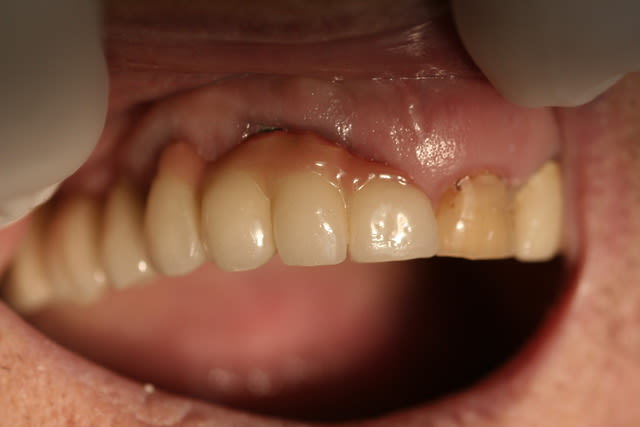

Un "bridge" 22-23-24 a été réalisé il y a 6 ans, sur 2 implants.

Cliniquement, si la 22 a été réalisée de façon classique, 23 et 24 sont montée sur une armature métallique en selle. En palatin, la selle avance sur le palais de 2 mm, mais en vestibulaire, on est plus à 8 mm de recouvrement.

La formation de tartre dans l'intrados de la selle donne une gencive inflammatoire, saignant spontanément au passage d'un fouloir rond. Je vous laisse voir les photos.

Il n'y a aucune doléance ou demande de la patiente concernant l'ensemble, ni fonctionnelle, ni esthétique.